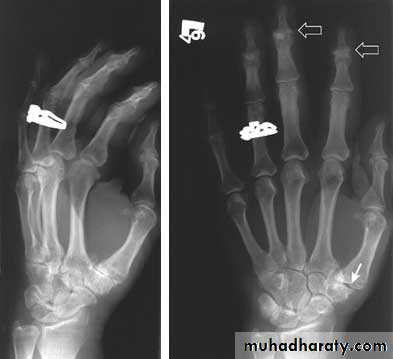

Another example of OA

Oblique and AP views

1st carpal metacarpal shows decreased joint space and subchondral sclerosis

2nd and 3rd DIP shows osteophytes and subchondral sclerosis (Heberden’s nodes)